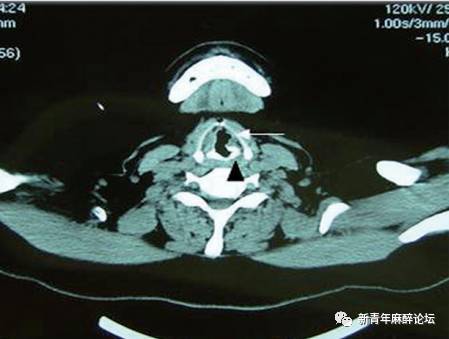

围术期出现环杓关节脱位,如何诊断处理?

环杓关节脱位

杓状软骨脱位

环杓关节脱位图片